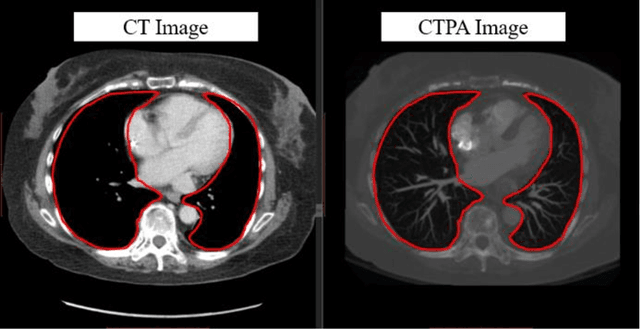

Abstract:The purpose of this research is to develop a system that generates simulated computed tomography pulmonary angiography (CTPA) images clinically for pulmonary embolism diagnoses. Nowadays, CTPA images are the gold standard computerized detection method to determine and identify the symptoms of pulmonary embolism (PE), although performing CTPA is harmful for patients and also expensive. Therefore, we aim to detect possible PE patients through CT images. The system will simulate CTPA images with deep learning models for the identification of PE patients' symptoms, providing physicians with another reference for determining PE patients. In this study, the simulated CTPA image generation system uses a generative antagonistic network to enhance the features of pulmonary vessels in the CT images to strengthen the reference value of the images and provide a basis for hospitals to judge PE patients. We used the CT images of 22 patients from National Cheng Kung University Hospital and the corresponding CTPA images as the training data for the task of simulating CTPA images and generated them using two sets of generative countermeasure networks. This study is expected to propose a new approach to the clinical diagnosis of pulmonary embolism, in which a deep learning network is used to assist in the complex screening process and to review the generated simulated CTPA images, allowing physicians to assess whether a patient needs to undergo detailed testing for CTPA, improving the speed of detection of pulmonary embolism and significantly reducing the number of undetected patients.

Abstract:This study was conducted to develop a computer-aided detection (CAD) system for triaging patients with pulmonary embolism (PE). The purpose of the system was to reduce the death rate during the waiting period. Computed tomography pulmonary angiography (CTPA) is used for PE diagnosis. Because CTPA reports require a radiologist to review the case and suggest further management, this creates a waiting period during which patients may die. Our proposed CAD method was thus designed to triage patients with PE from those without PE. In contrast to related studies involving CAD systems that identify key PE lesion images to expedite PE diagnosis, our system comprises a novel classification-model ensemble for PE detection and a segmentation model for PE lesion labeling. The models were trained using data from National Cheng Kung University Hospital and open resources. The classification model yielded 0.73 for receiver operating characteristic curve (accuracy = 0.85), while the mean intersection over union was 0.689 for the segmentation model. The proposed CAD system can distinguish between patients with and without PE and automatically label PE lesions to expedite PE diagnosis